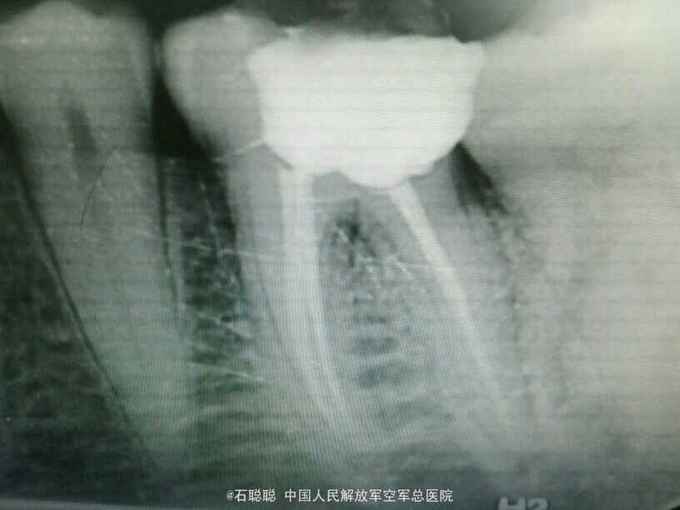

诊断:左下6急性牙髓炎 治疗计划:左下6根管治疗后冠修复 处置:左下6利多卡因局麻下开髓,揭顶,探及近颊,近舌,远中3个根管口,冲洗,干燥,置失活剂,氧化锌暂封 一周后复诊 诉无不适,检查左下6氧化锌暂封完整在位,叩痛-,不松动,牙龈未见异常 处置:左下6去除氧化锌暂封,测工作长度,近颊=18mm,近舌19mm,扩大至30#,远中=20mm,扩大至35#,冲洗,干燥,置CP棉球,氧化锌暂封 一周后复诊:左下6叩痛-,不松动,氧化锌完整在位 处:去除左下6氧化锌暂封,试主尖,冷侧压充填,氧化锌暂封 医嘱:一周后修复左下6

讨论:这是一个典型急性牙髓炎的病历,左下6近中两个根管,远中一个扁形的粗大根管,常规扩大成形后,冷侧压充填,由于远中壁缺损较大,但仍位于龈上2mm,建议全冠修复,恢复患牙咀嚼功能